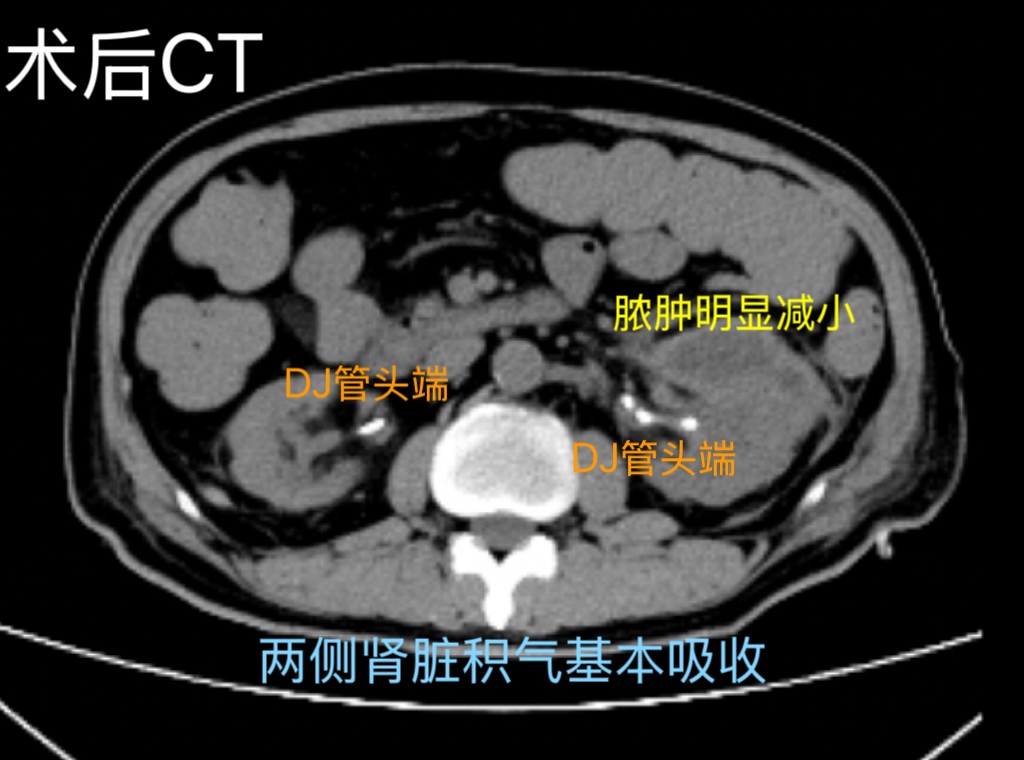

随后,团队顺利为患者实施双侧经皮肾镜手术+双侧输尿管DJ管置入术+左肾周脓肿引流术,术中彻底清除肾内大量脓苔以及结石,术后有效引流脓性尿液,全程操作精准高效。术后患者生命体征平稳,未出现感染性休克、出血等并发症,肾功能明显好转,肌酐从术前316mmol/L降至153mmol/L,救治效果显著。